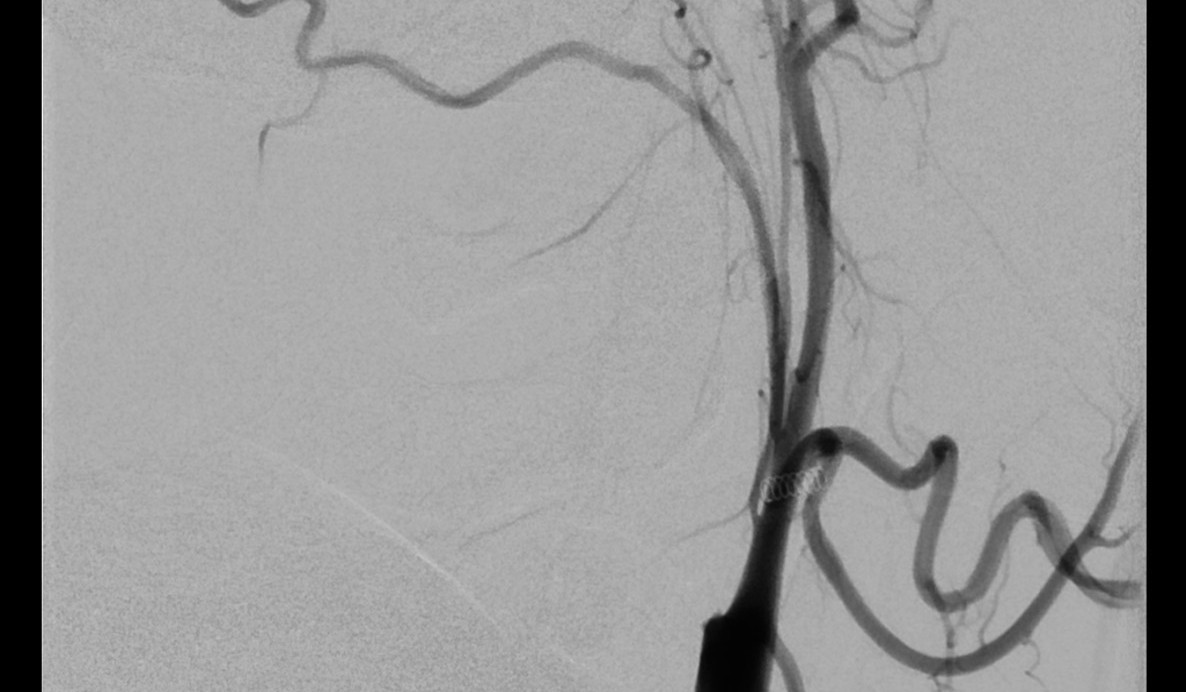

Eingeliefert wird Mathias Zierke vom Rettungsdienst als akuter Notfall in die Medizinische Universität Lausitz – Carl Thiem (MUL – CT), die aufgrund ihrer zertifizierten überregionalen Schlaganfallstation auf genau solche Fälle spezialisiert ist. „Auf der Fahrt bin ich kurz wachgeworden. Ansonsten habe ich ganz schwache Erinnerungen an den Morgen“, sagt Zierke. In der Zentralen Notaufnahme wird der Forster vom Team der Neurologie und Radiologie übernommen. Aufgrund der Symptomatik wird von einem Schlaganfall ausgegangen und eine Computertomografie des Kopfes und der hirnversorgenden Arterien initiiert. Nach Auswertung der Untersuchung bestätigt sich der Verdacht: Verschluss der mittleren Hirnarterie durch einen Thrombus, der sich an der hochgradigen Verengung der Halsschlagader gebildet hat. Mathias Zierke wird nach medikamentöser Behandlung mit einem blutgerinnselauflösenden Medikament umgehend zur weiteren minimalinvasiven Eröffnung des Verschlusses in die Angiografie gebracht.

„In einem minimalinvasiven Eingriff führen wir für gewöhnlich einen Katheter von der Leistenarterie ein und navigieren ihn über einen dünnen Draht bis unmittelbar vor den Thrombus in der verschlossenen Hirnarterie“, erläutert Dr. Stefan Kliesch, Chefarzt Diagnostische & Interventionelle Neuroradiologie an der MUL – CT, „wobei wir bei Herrn Zierke die für den Thrombus ursächliche hochgradige Verengung der zuführenden Halsarterie schnell passieren konnten.“

Der Thrombus in der Hirnarterie kann entfernt und die zugrundeliegende Gefäßverengung am Hals mit einem Stent und einem kleinen Ballon geweitet werden.

„Der gesamte Eingriff dauert dabei nicht einmal eine Stunde und Herr Zierke wird noch auf dem Untersuchungstisch aus der Narkose erweckt“, sagt Dr. Kliesch. Nach dem Eingriff wird er zur Risikoabklärung auf die Stroke Unit des Klinikums verbracht. „Diese hochspezialisierte interventionelle Behandlung des Schlaganfalls kann nur in optimaler Zusammenarbeit von Neurologie, Anästhesie und Neuroradiologie erfolgen“, ergänzt Dr. Antje Herwig, leitende Oberärztin der Klinik für Neurologie.